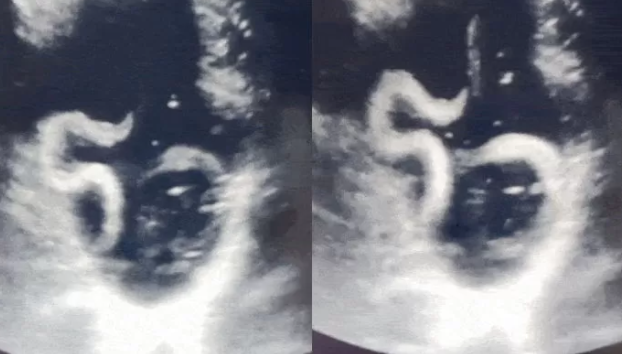

심지어 병원에서 검사를 하던 의사는 깜짝 놀라고 말았는데요. 그 이유가 바로 위장 속에 있던 큰 기생충이 살아서 움직이고 있었기 때문입니다. 기생충의 움직임이 초음파에 잡히는 등 의사도 처음 보는 일로 놀랐다고 합니다. 위장 속에서 살아서 움직이는 기생충을 봤다는 것은 충격 그 자체입니다.

병원에 찾았을 때 기생충의 여부는 초음파 검사를 통해 알 수 있고 위나 장에 기생충이 기생하여 살고 있을 때에는 반드시 알맞은 치료법으로 치료를 해야 하고 심한 경우에 수술을 진행할 수도 있습니다.